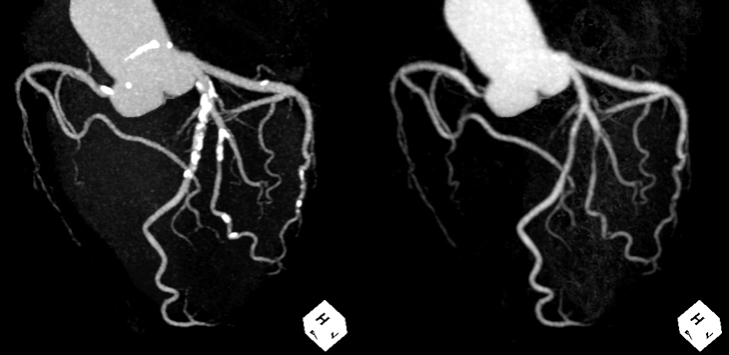

サブトラクション冠動脈CT

これまで、CTでは評価が難しいとされている冠動脈の強い石灰化部位やステント治療部位において、我々が考案した特殊な撮影(test bolus tracking法)および画像処理技術を用いて評価可能な画像を可能な限り提供しています。

通常の画像(左)に比べ、石灰化(白い部分)を除去した画像(右)では血管狭窄の有無が明瞭に評価できます。